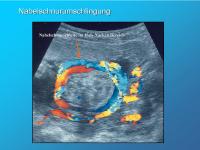

Nabelschnurumschlingung

Abbildung 4

Keywords: FarbdopplerMangelversorgungNabelschnurumschlingung